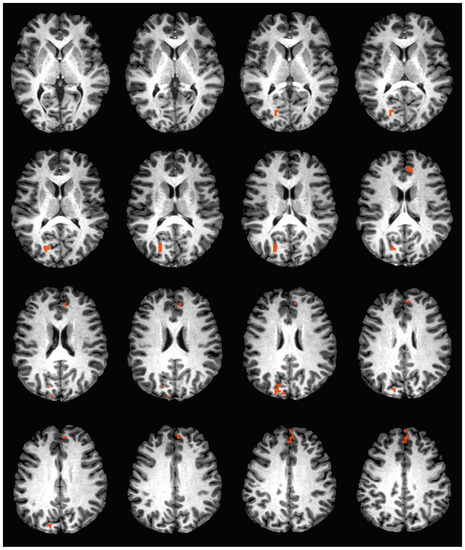

During the hedonic evaluation of caffeine, caffeine non-consumers had significantly greater neuronal activation in the right cuneus, right precuneus, left anterior cingulate, medial frontal gyrus, and left superior frontal gyrus (See Table 4 and Figure 2).

During the hedonic evaluation of saccharin, caffeine non-consumers had significantly lower neuronal activation than caffeine consumers in the middle temporal gyrus, inferior temporal gyrus, middle occipital gyrus, right fusiform gyrus, right lingual gyrus, and right cuneus (See Table 5 and Figure 3).

During the hedonic evaluation of sucrose, caffeine non-consumers had significantly greater neuronal activation in the anterior cingulate, medial frontal gyrus, right superior frontal gyrus, OFC BA 10, posterior cingulate, cingulate gyrus, and precuneus (See Table 6 and Figure 4).

Figure 2. Brain activation during the hedonic evaluation of caffeine. Orange indicates areas where caffeine non-consumers had significantly greater activation in comparison to caffeine consumers.

Figure 3. Brain activation during the hedonic evaluation of saccharin. Blue indicates areas where caffeine consumers had significantly greater activation in comparison to caffeine non-consumers.

Figure 4. Brain activation during the hedonic evaluation of sucrose. Orange indicates areas where caffeine non-consumers had significantly greater activation in comparison to caffeine consumers.